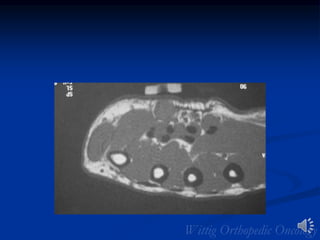

MRI:Leiomyosarcoma of Vastus

Medialis Muscle

CT Scan Leiomyosarcoma Vastus

Leiomyosarcoma

• Remainder of lesions in GU and GI tracts

• 5th and 6th decades

• Metastases common

• Imaging similar to MFH/fibrosarcoma

• Extremity lesions usually intramuscular

• Central necrosis/hemorrhage common

• Calcification/osseous invasion rare